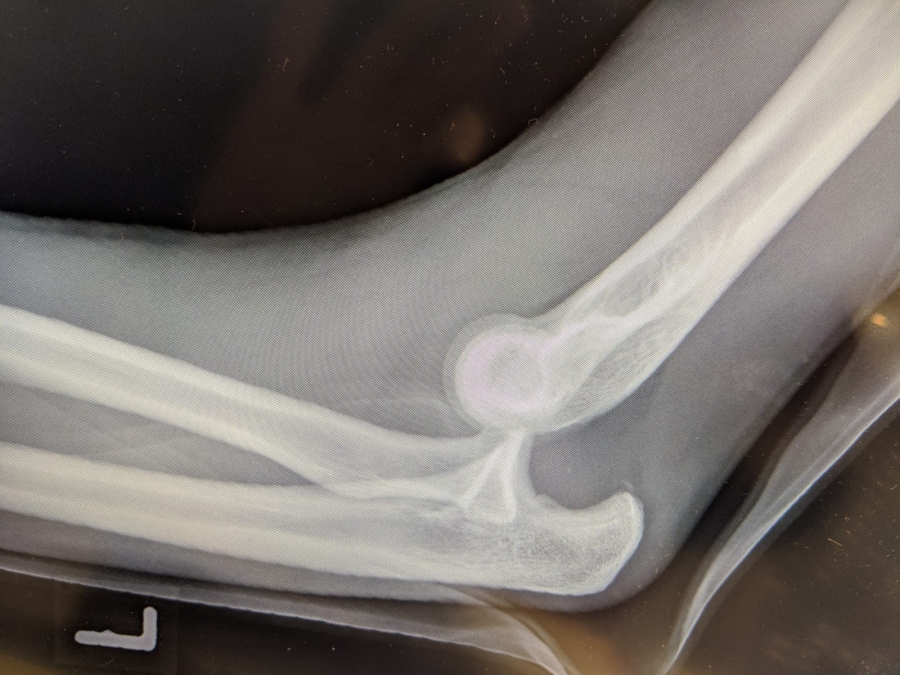

Es war der 30. Dezember des vergangenen Jahres als der Sportler des LAZ Soest wie so oft auf der Hochsprungmatte in der Dortmunder Helmut-Körnig-Halle seine Turneinheit absolvierte. „Ich habe mich in der Luft etwas zu schnell gedreht, bin dann in Rücklage gelandet, von der Matte gefallen und habe mich schließlich auf dem Arm abgestützt“, erinnert sich der 24-Jährige heute. „Als der Schmerz nicht aufhörte wusste ich: Das ist etwas Schlimmeres.“ Wenig später im Krankenhaus kam dann die Diagnose: „Luxation im linken Ellenbogengelenk“. Sprich: Das Gelenk ist nicht mehr dort, wo es hingehört, es ist ausgerenkt. „Das ist eine richtig schwere Verletzung“, erfuhr Wendrich spätestens nach dem Blick auf die Röntgenbilder. Auch das Radiusköpfchen, ein Knochen am oberen Ende der Speiche, brach bei dem Sturz. Als Wendrich das Krankenhaus verließ, waren Ober- und Unterarm im 90-Grad-Winkel eingegipst und es war klar: Die Hallensaison ist gelaufen.